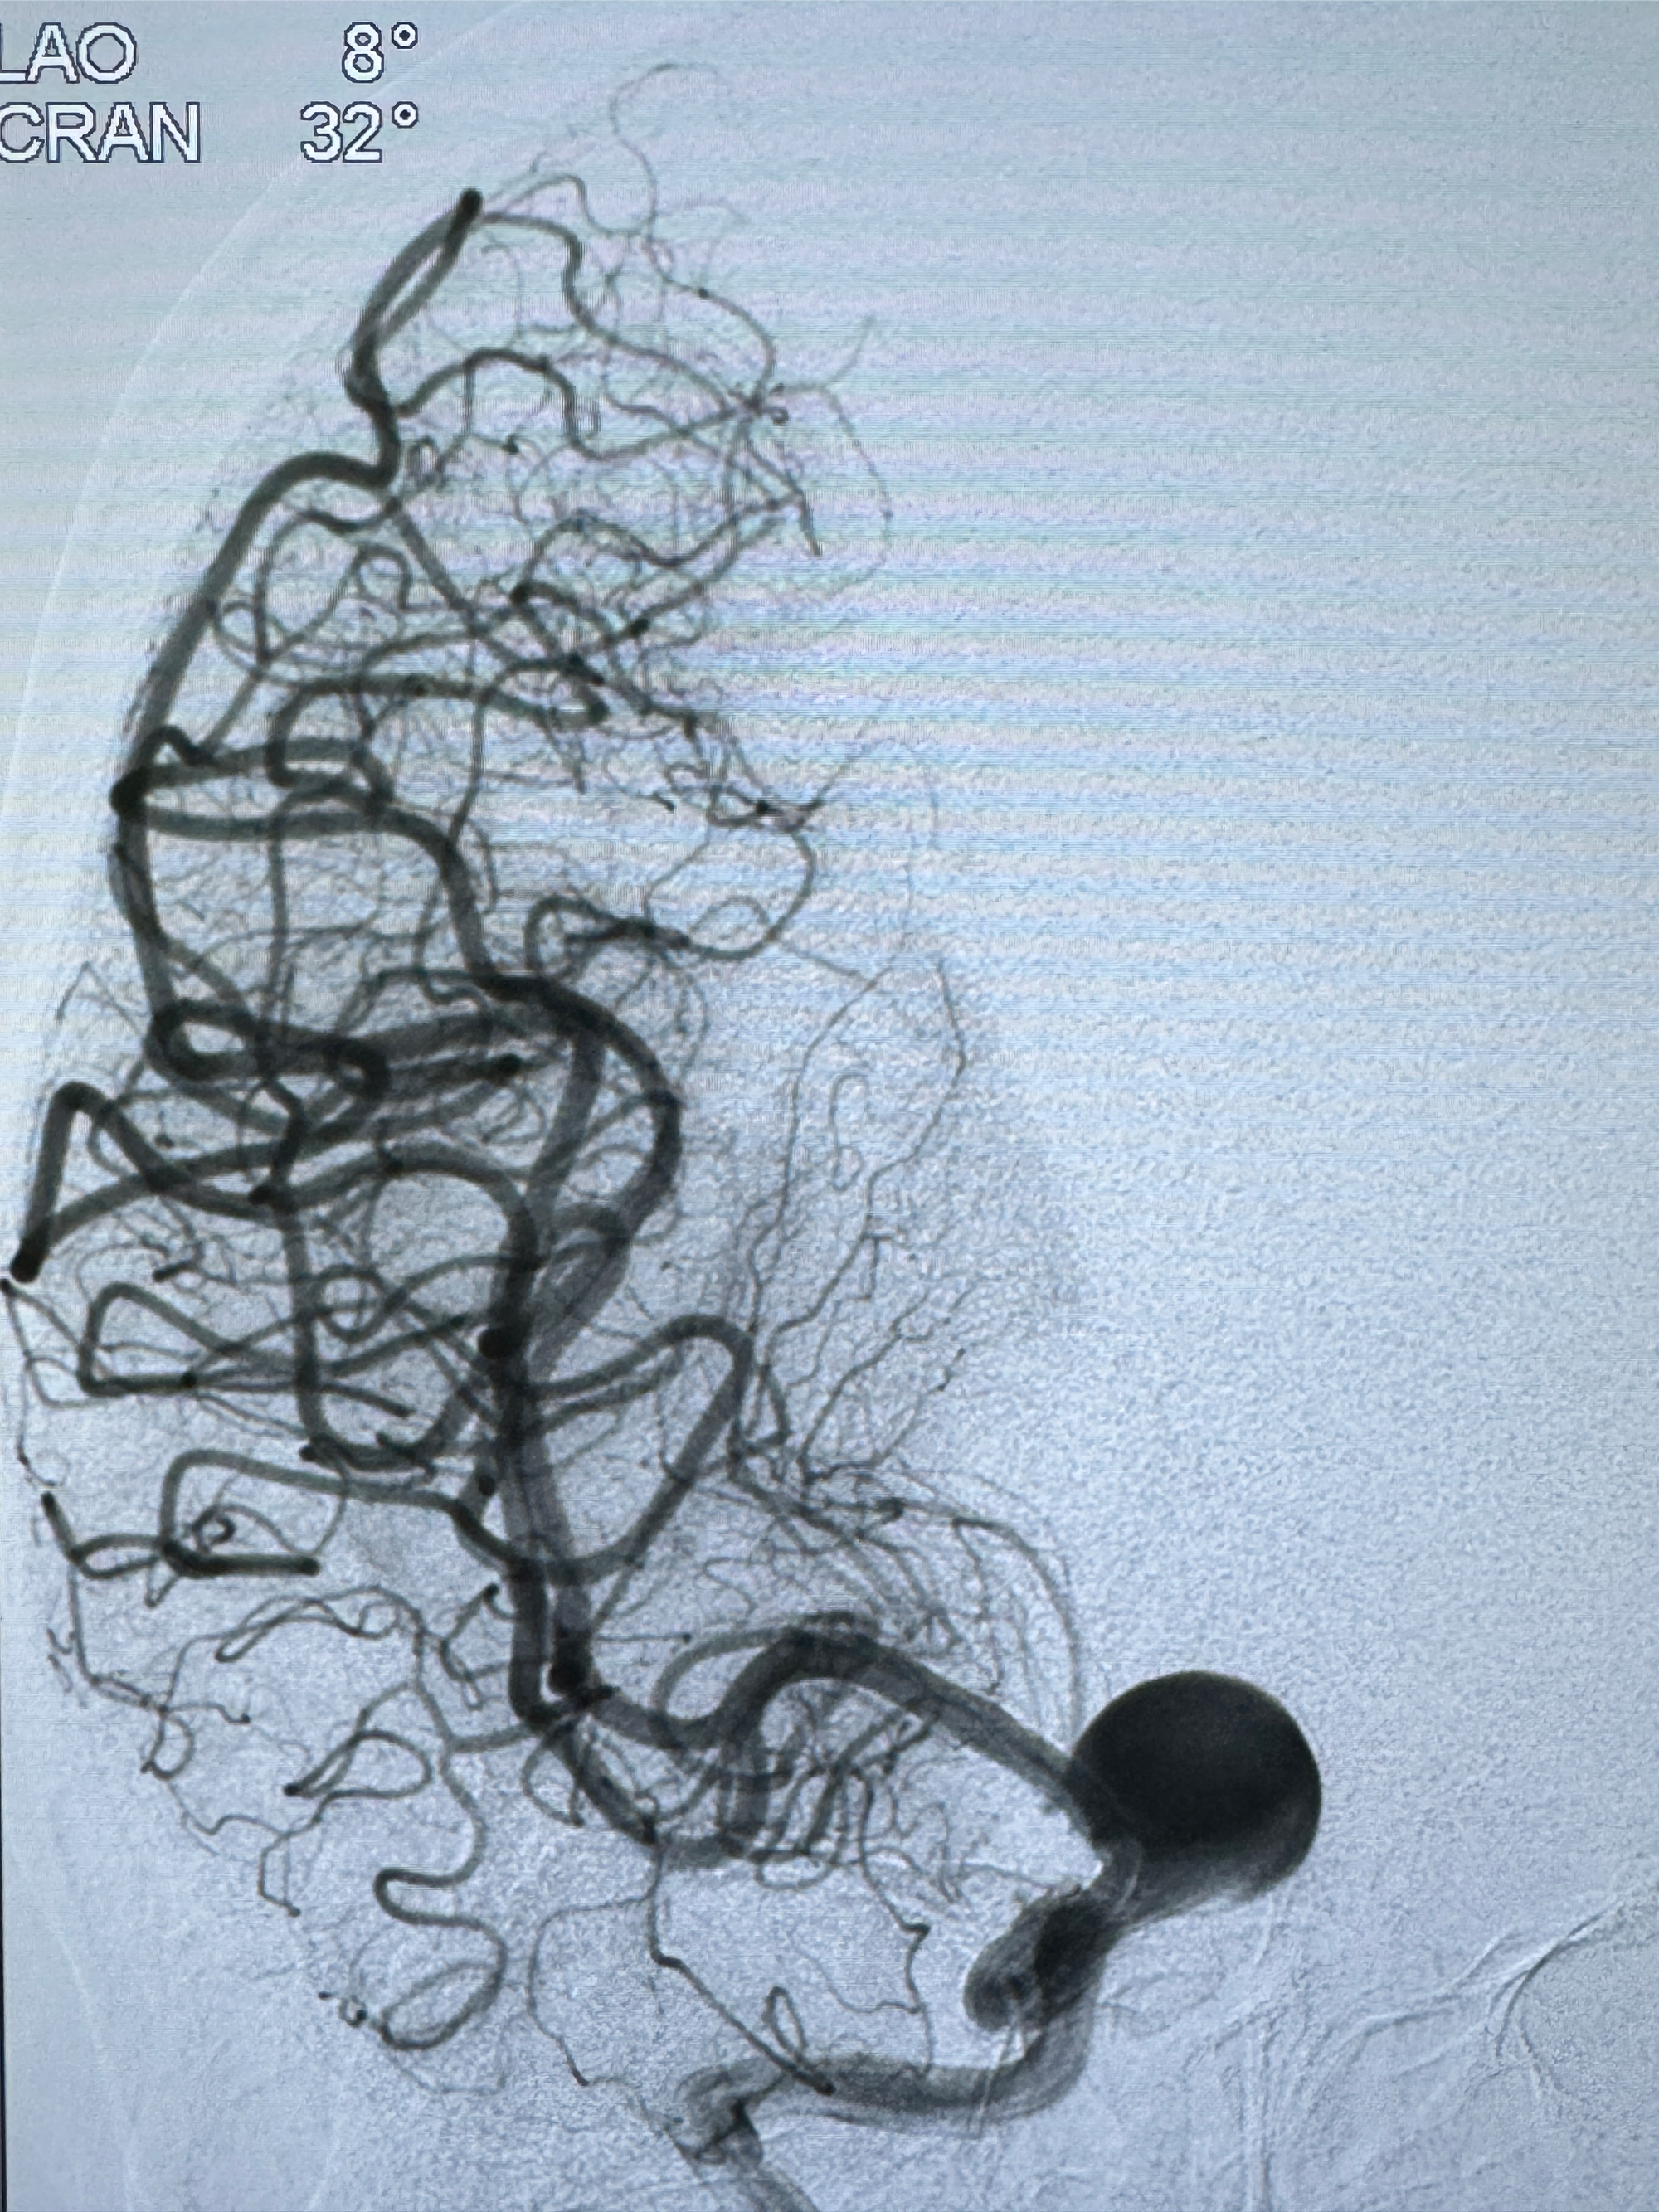

2023-12-08外院DSA:右侧颈眼动脉瘤,约13*12mm大小,压颈试验显示左右向及后向前代偿可

2023-12-18全麻下行DSA➕密网支架植入备弹簧圈辅助栓塞

旋转3D展示动脉瘤局部的血管构筑

测量动脉瘤的大小:16*13.8*7.6mm大小,较原先变大,考虑双抗后瘤内血栓溶解可能